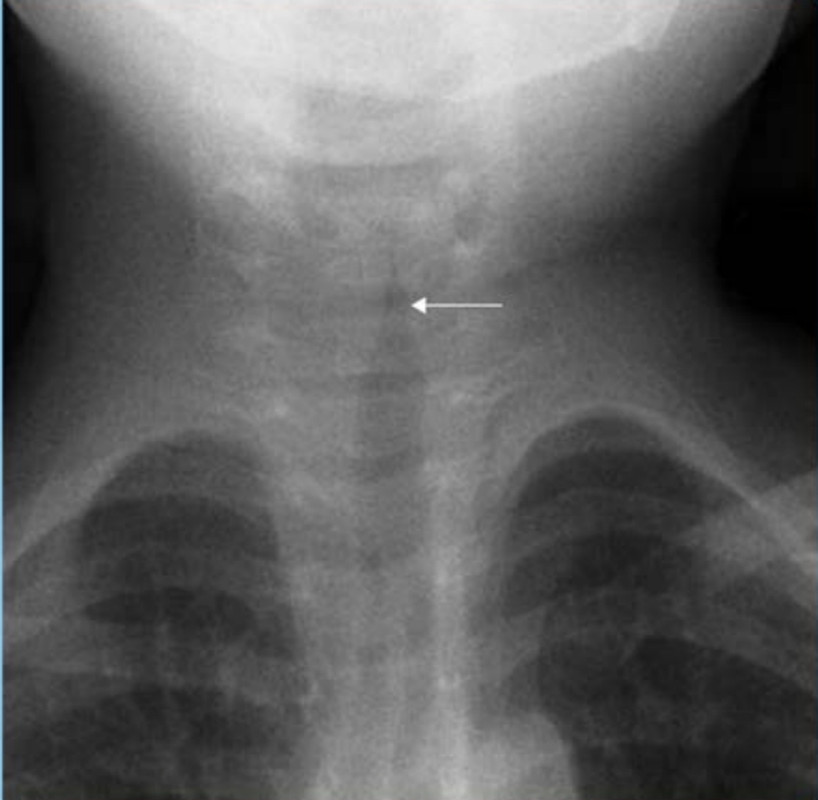

ENT PYQs